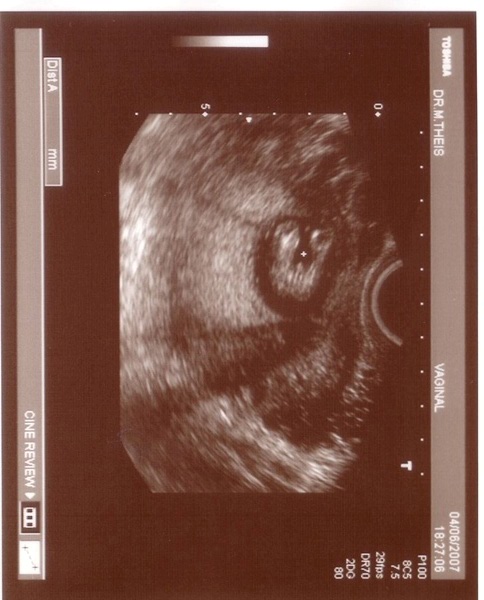

Köszönöm kérdésed, egyenlőre jól vagyok. Néha érzek hányingert. De eddig én a 7. hét környékén szoktam szarabbul lenni. Akkor napi 2 róka beköszöntött.

Én erről a PCO-ról, itt hallottam először.